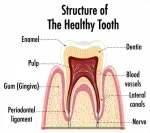

На снимке явный пульпит. В 90% случаях нервы приходится удалять. К тому же, при препарировании кариеса необходимо убрать все кариозные отложения. Зачастую терапевт проваливается в камеру, хотя по снимку зуб можно сохранить живым.

Не переживайте, это не ошибка доктора, а правильный диагноз. К тому же, тот факт, что зуб не беспокоил до лечения не имеет в этом случае никакого значения. Дело в том, что даже при депульпации зуба, лучше это делать при небольшом кариозном отложении, так как в противном случае, после эндодонтического лечения приходится протезироваться. Всё вы сделали правильно!